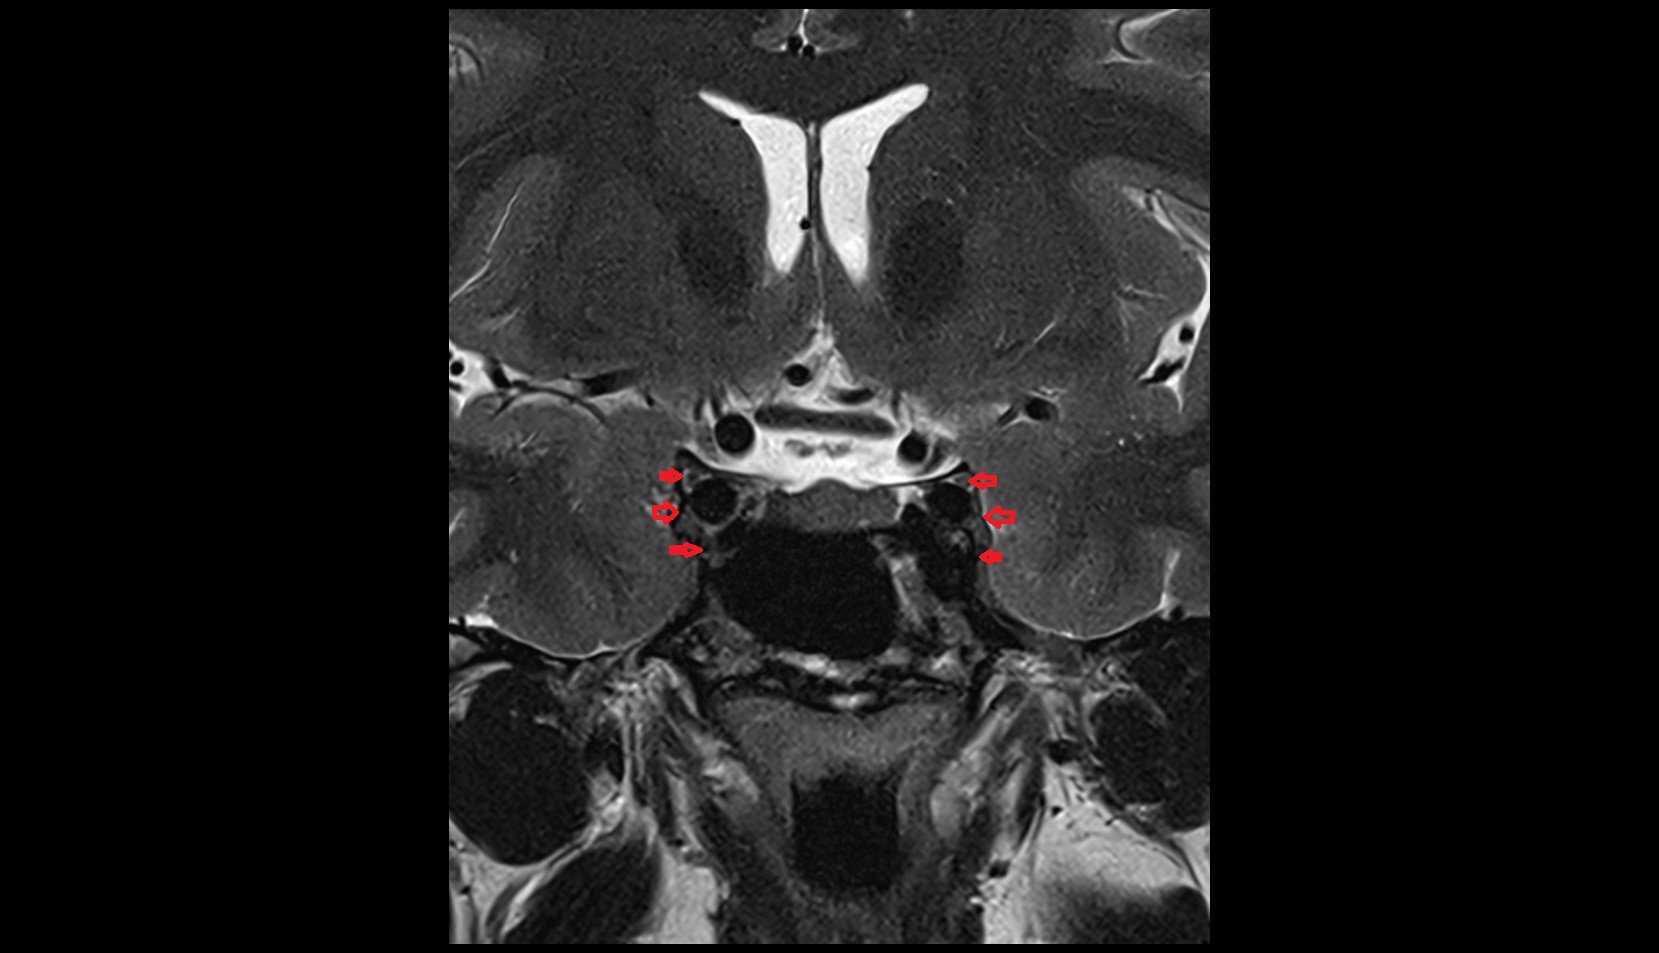

- Exit foramina